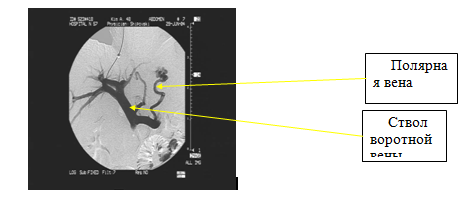

TIPS является малоинвазивной хирургической операцией, проводимой под контролем рентгеноскопии и включает в себя ряд эндоваскулярных процедур в определенной последовательности- после пункции яремной вены с помощью сосудистых стентов (голометаллических или стент-графтов) формируется внутрипеченочное соустье между крупными печеночными венами и ветвями воротной вены. В результате использования TIPS сохраняется гепатопетальный кровоток и осуществляется отчетливая портальная декомпрессия. Успех процедуры во многом зависит от квалификации оперирующего хирурга и учёта им индивидуальных анатомических особенностей пациента (рис. 15).

4. Доступ в воротную вену. Для облегчения этого этапа операции целесообразно использовать УЗИ наведение пункционной иглы и карбоксипортографию (рис.16 и 17).

Рисунок 16. Портография с использованием СО2.(карбоксипортография)

Рисунок 17. Трансъюгулярная портография

7. Портография. После стентирования выполняется портография для визуализации портосистемного анастомоза. Кроме того, портография может показать наличие таких осложнений как: пристеночный тромбоз, перекрут стента. Наиболее информативна контрольная портография при использовании 3D-моделирования. (рис.18)

Рисунок 18. Функционирующий портосистемный шунт.